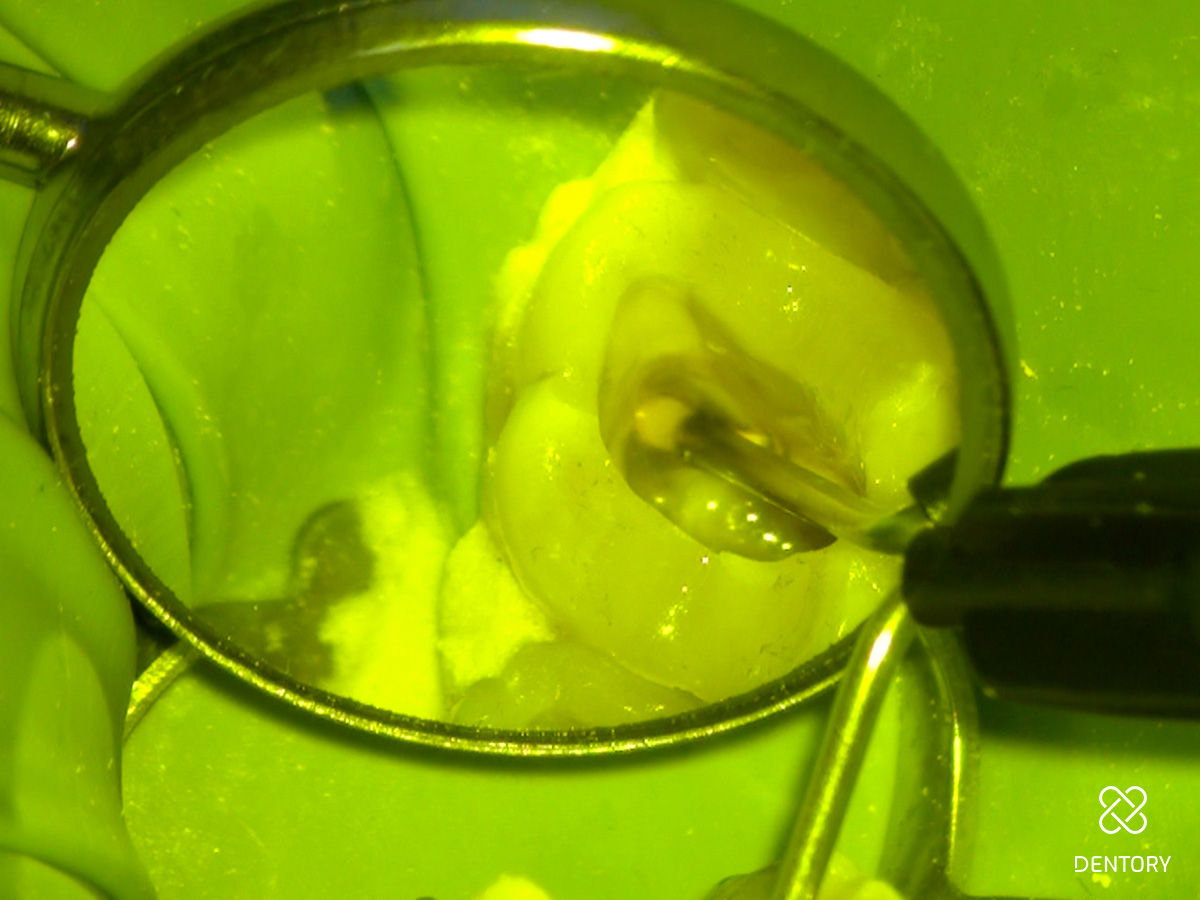

Abbildung 6

Der weißliche mb2-Kanaleingang hebt sich vom dunkleren Pulpenboden ab.